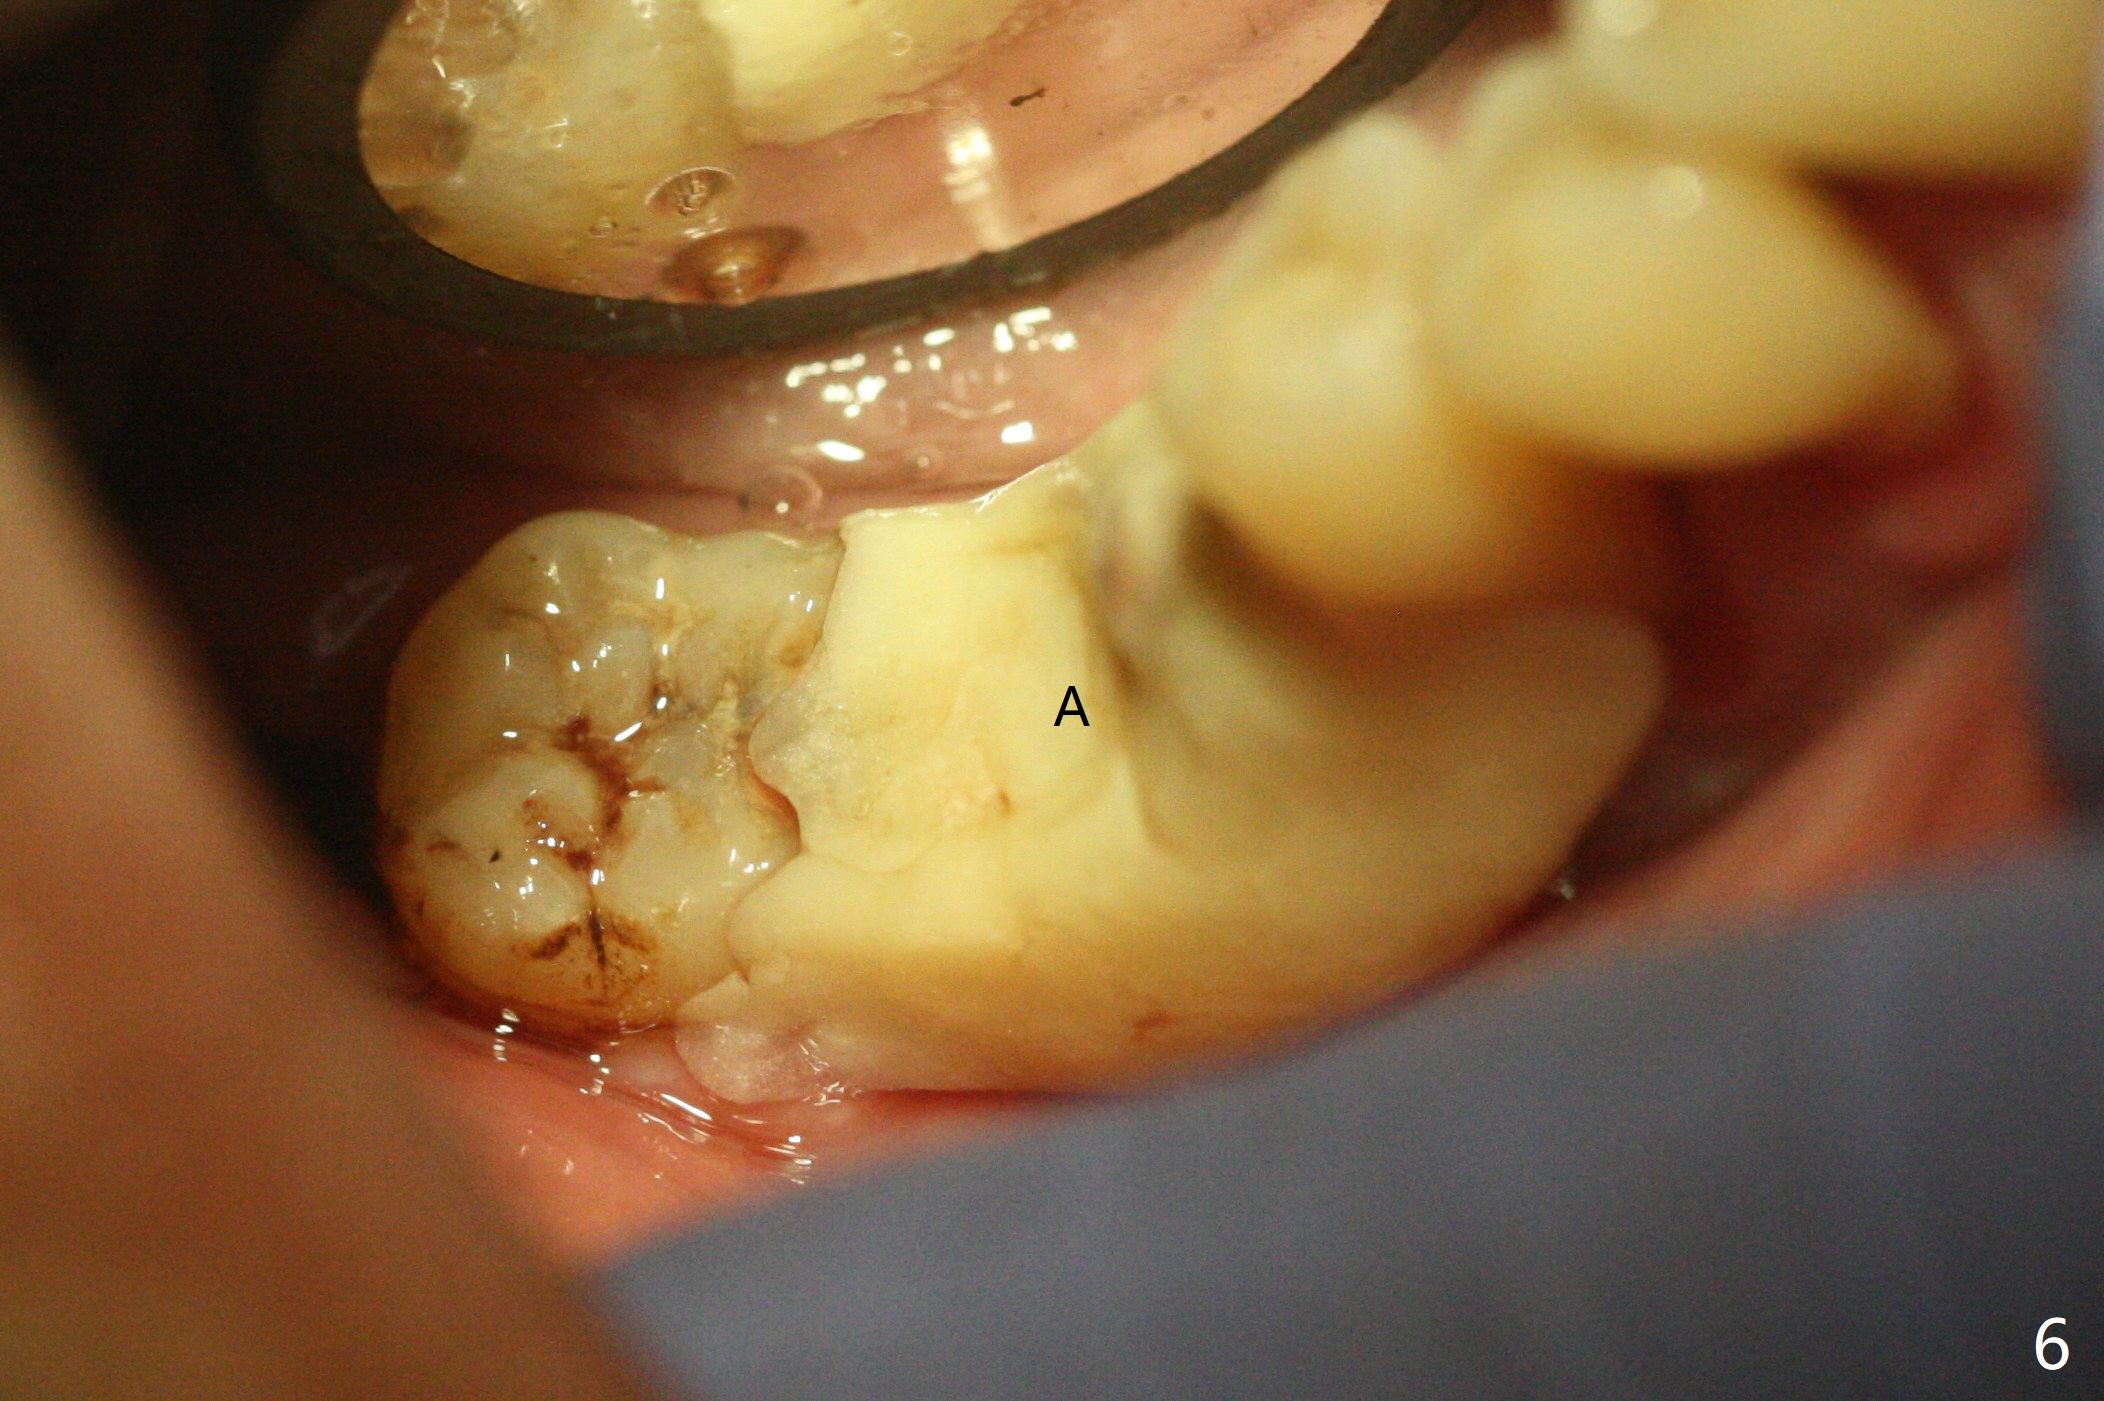

69岁男因疼痛回来拔除右下6,保留中隔牙龈,在近中牙槽窝开始钻洞(图一:空箭头),但是由于近中斜坡,最终1.6毫米先锋钻远中偏移。远中骨质高度减少,原先计划近中牙槽窝深度7毫米,当钻头滑到接近中隔,钻头尖口内接近神经,病人感到疼痛(浸润麻醉)。block anesthesia下,放置4x9毫米报废植体(图二),口内显得太长,所以选择4x7毫米植体(图三),基台就位。第一次放置骨粉远中不足(图四:*),再次植骨,好像达到目的(图五:*)。覆盖PRF膜后,放置树脂敷料(图六:A)。